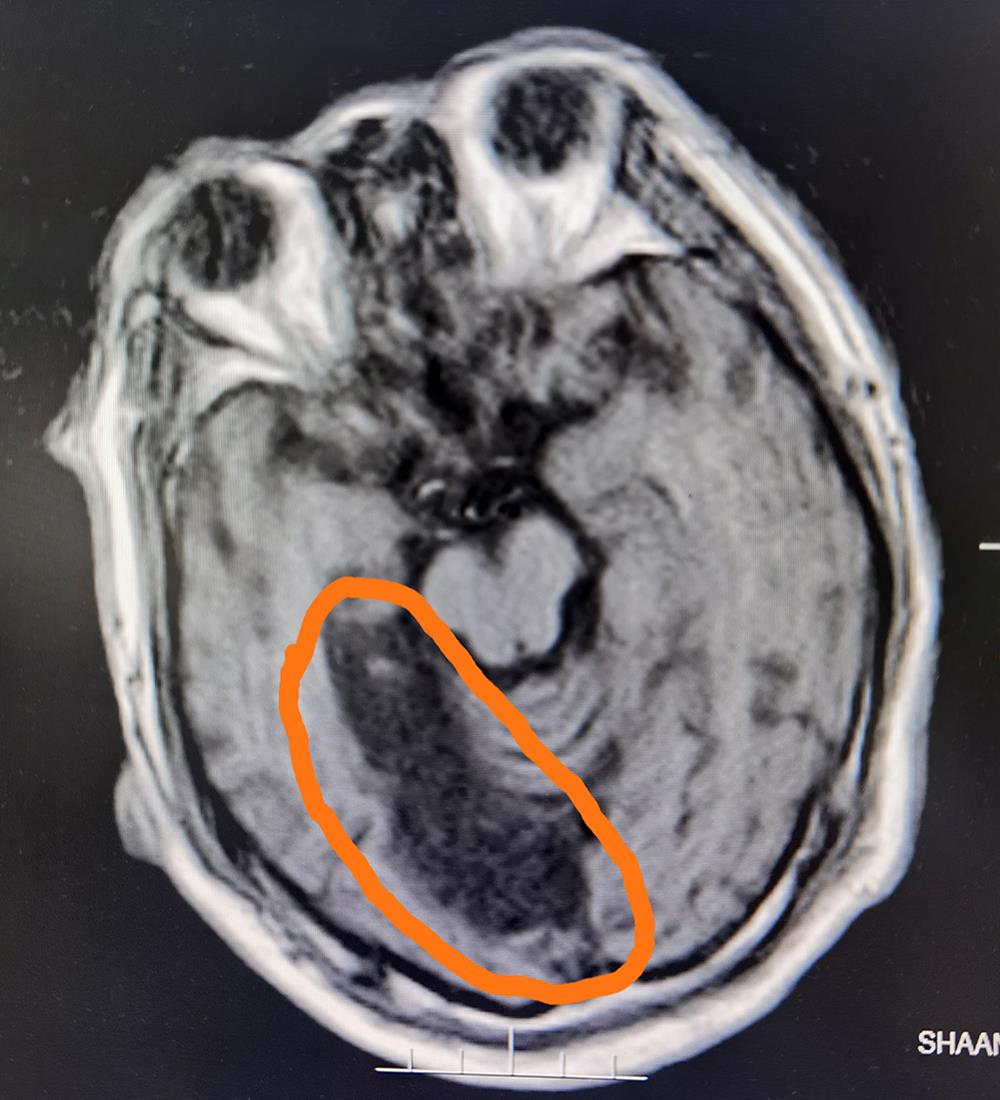

今年54岁的男性患者因突发意识不清、烦躁、完全不能言语、右侧肢体偏瘫,被工友发现后紧急从单位送来榆林二院求诊。在卒中中心诊查后急行头颅影像检查,发现该患者左侧大面积脑梗死,右侧大面积脑软化灶,因其意识不清,烦躁,核磁血管检查不能配合,紧急收住脑科医院神经内科一病区进行救治。